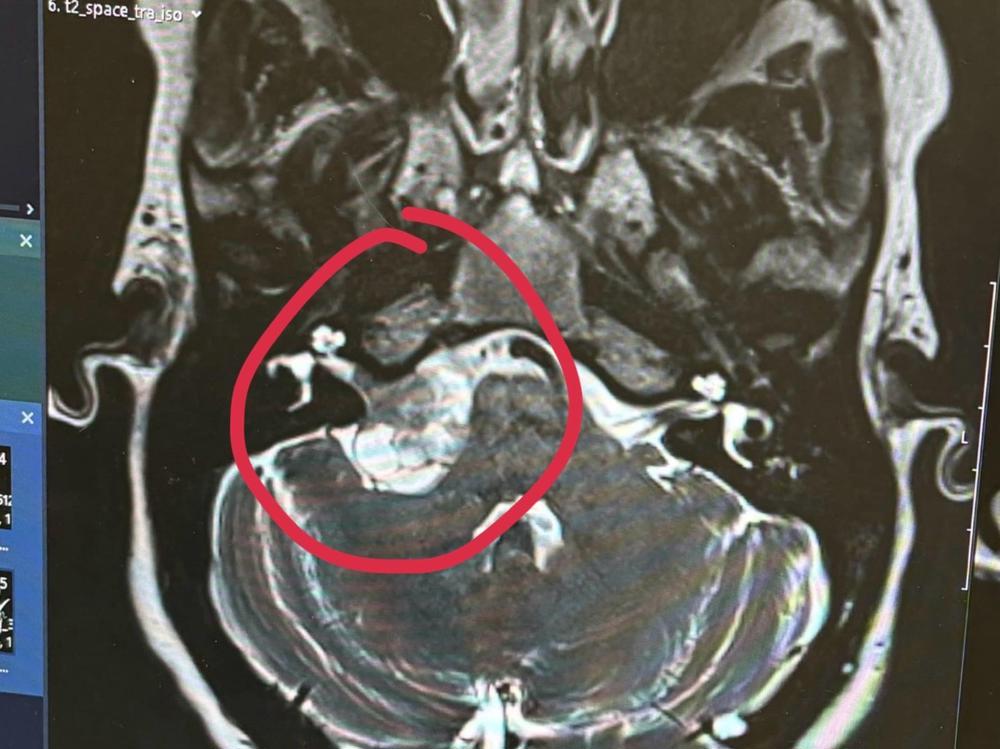

Things still weren’t right so she saw a GP in London who ordered an MRI on her head. Turns out there is a tumor growing along the nerves that go to her ear in her brain. They believe it’s not cancerous but it is growing and could result in pressing on other nerves in her brain which could lead to facial paralysis.